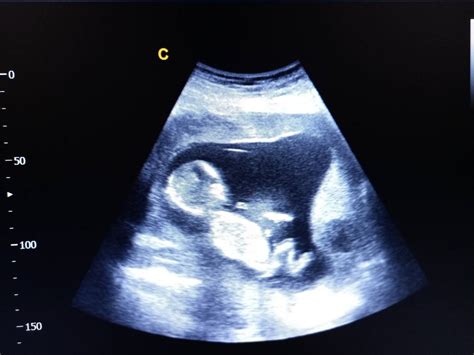

După aproape o lună de tratament (Utrogestan, No-Spa, acid folic), Buburuza a revenit pentru o nouă ecografie. Deși sarcina evolua normal, cu un bebe activ, medicul a constatat o creștere semnificativă a desprinderii, ajungând la 12 mm. Această veste, deși medicul a asigurat că nu este grav și a recomandat odihnă și evitarea contactului sexual, a generat din nou teamă.

Buburuza a solicitat din nou sfaturi suplimentare, oferind detalii din ecografie:

- Sarcina: 10,4 săptămâni

- CRL (Lungimea craniului-caudală): 35,7 mm

- LA (Lichid amniotic): normal

- BCF (Bătăile cordului fetal): (nedescifrabil)

- Placenta anterioară, jos inserată, prezintă dezlipire mare la marginea inferioară de 12 mm.